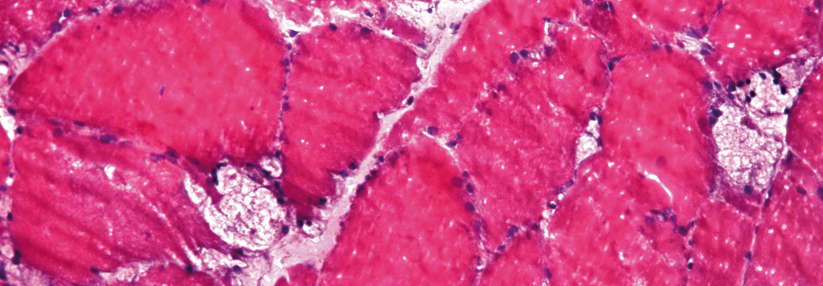

Neues EET-Medikament bei Morbus Pompe kann überzeugen

Eine Weiterentwicklung der bereits etablierten Alglucosidase Alfa kann Fortschritte bei der Enzymersatztherapie beim M. Pompe erzielen. Patienten…